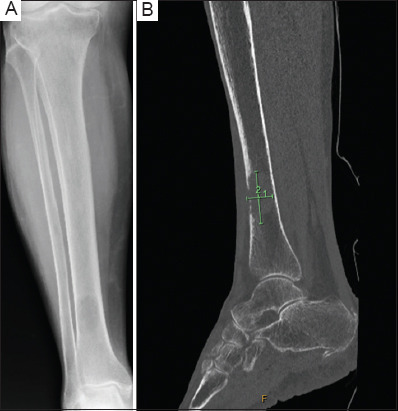

背景:膀胱癌(BCa)经常转移到骨骼,通常影响脊柱和骨盆。病例介绍:本文报告一例罕见的广泛胫骨远端转移病例,患者为84岁女性,患有侵袭性高级别尿路上皮癌,踝关节疼痛迅速进展,活动能力降低。影像学和活检证实转移性尿路上皮癌在胫骨,这是管理手术固定和姑息性放疗。虽然BCa的骨转移通常会影响其他部位,但临床医生应考虑非典型部位,如胫骨,患者有不明原因的骨痛。结论:早期诊断和干预对改善患者预后和生活质量至关重要。

Case presentation: Presented here is a case of rare extensive distal tibia metastasis in an 84-year-old female with invasive high-grade urothelial carcinoma, who suffered from rapidly progressive ankle pain and reduced mobility. Imaging and biopsy confirmed metastatic urothelial carcinoma in the tibia, which was managed with surgical fixation and palliative radiotherapy. Although bone metastases in BCa commonly affect other sites, clinicians should consider atypical locations like the tibia in patients with unexplained bone pain.